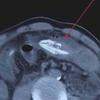

image Homem coloca enguia no ânus para tratar constipação e quase vai à óbito

Prática considerada irregular acabou provocando um problema ainda maior